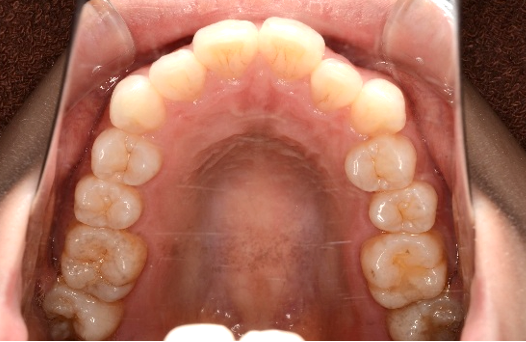

出っ歯治療症例

上顎前突(出っ歯)

歯が並ぶためのスペースが足りず上の前歯が前方に倒れてしまうことや下顎の成長が遅れており小さいことが原因となります。